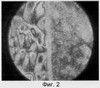

Пример 2. На поверхность стеклянной пластины из раствора наносят тонкий слой полианилина, затем образец помещают на две минуты в 0.03% водный раствор сыворотки, содержащий антитела к вирусу гриппа типа В. После этого испытуемый образец помещают в дистиллированную воду и промывают там две минуты для удаления неиммобилизованных антител. Далее образец на 2 минуты погружают наполовину в раствор, содержащий вирусы гриппа типа А (гетерогенная система), после чего 5 минут отмывают в воде, а затем высушивают на воздухе при комнатной температуре в течение 10 минут. Всю поверхность пленки после проведения этих операций обрабатывают раствором жидкого кристалла метоксибензилиденбутиланилина (МББА) в этиловом спирте – образец и после испарения растворителя помещают в поле зрения поляризационного микроскопа, в котором поляризатор и анализатор размещены под углом, например, в 90°. В результате проведения этих операций на тест-пластине формируются две области (Фиг.2, диаметр поля наблюдения 800 нм). На левой стороне поля на Фиг.2 находится область пленки полианилина, последовательно обработанная антителом к вирусу гриппа типа В и затем вирусом гриппа типа А (гетерогенная система), в то время как на правой стороне находится область пленки полианилина, обработанная только антителом к вирусу гриппа типа В. Таким образом, при несовпадении типов антитела и антигена на поверхности полианилинового слоя, а также при закреплении только антигена (вируса) наблюдаемая в поляризационном микроскопе картина сильно отличается от той, которая наблюдалась в первом примере для гомологичной системе при совпадении типов вируса и антитела.